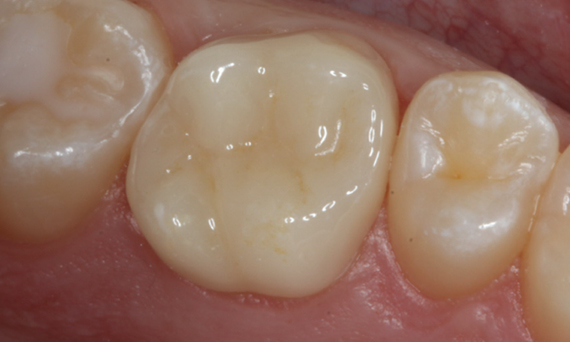

After

Chairside-fabricated restoration made from an advanced lithium-disilicate ceramic CEREC Tessera.